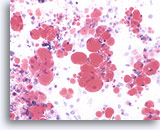

Figure 161

Macrophages

In cases of lipoid, or aspiration pneumonia the macrophages contain multiple complex lipid vacuoles.

Macrophages

In cases of lipoid, or aspiration pneumonia the macrophages contain multiple complex lipid vacuoles.

Figure 161

Macrophages

In cases of lipoid, or aspiration pneumonia the macrophages contain multiple complex lipid vacuoles.

Macrophages

In cases of lipoid, or aspiration pneumonia the macrophages contain multiple complex lipid vacuoles.